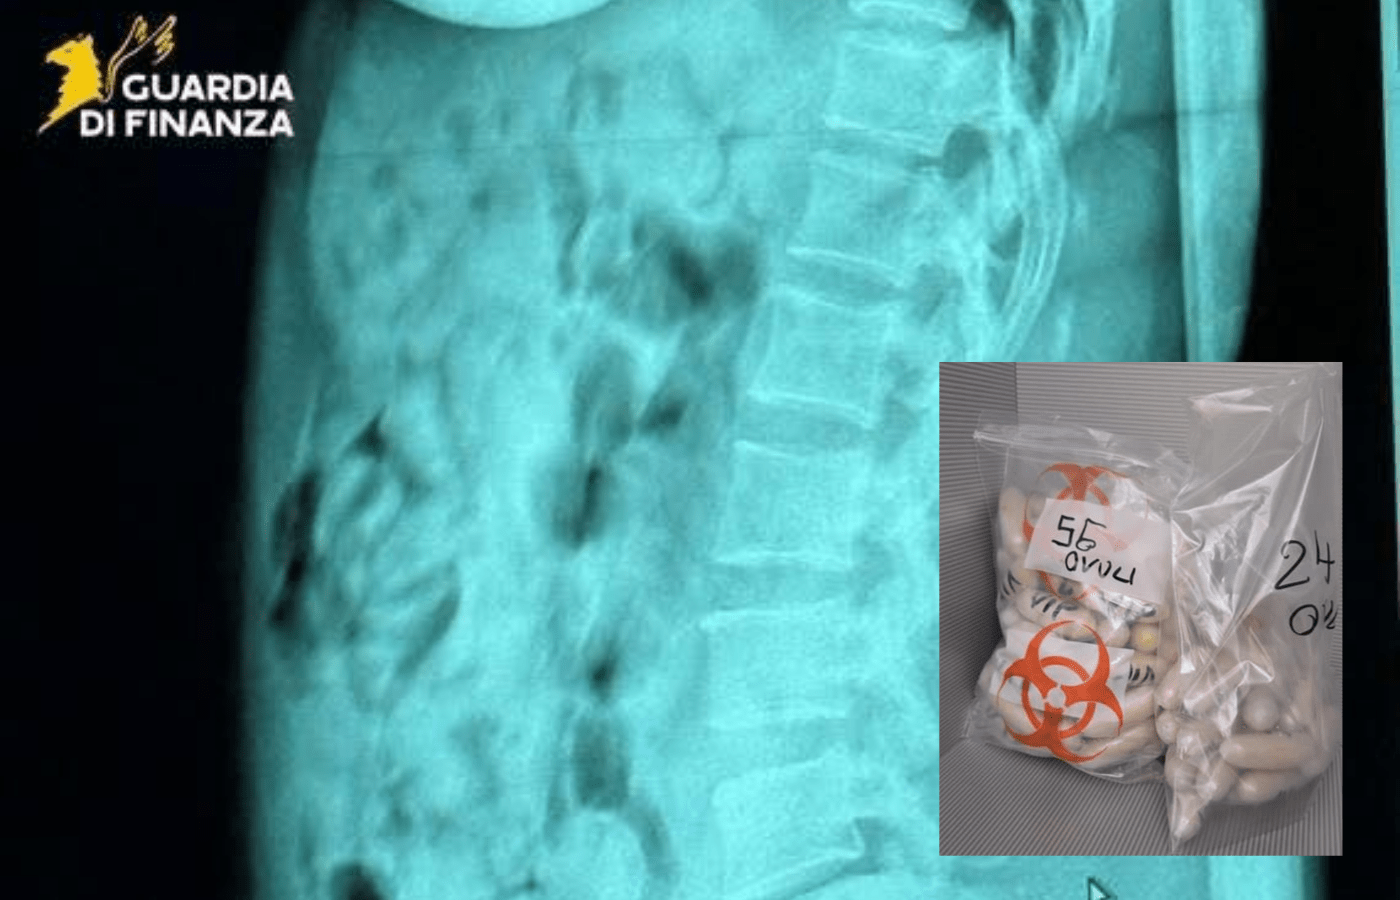

Gli esami radiologici effettuati all’ospedale Papa Giovanni XXIII di Bergamo hanno confermato la presenza di 120 involucri plastici avvolti in nastro adesivo. Una volta espulsi, i pacchetti sono risultati contenere eroina per un peso complessivo di 1,393 chili.